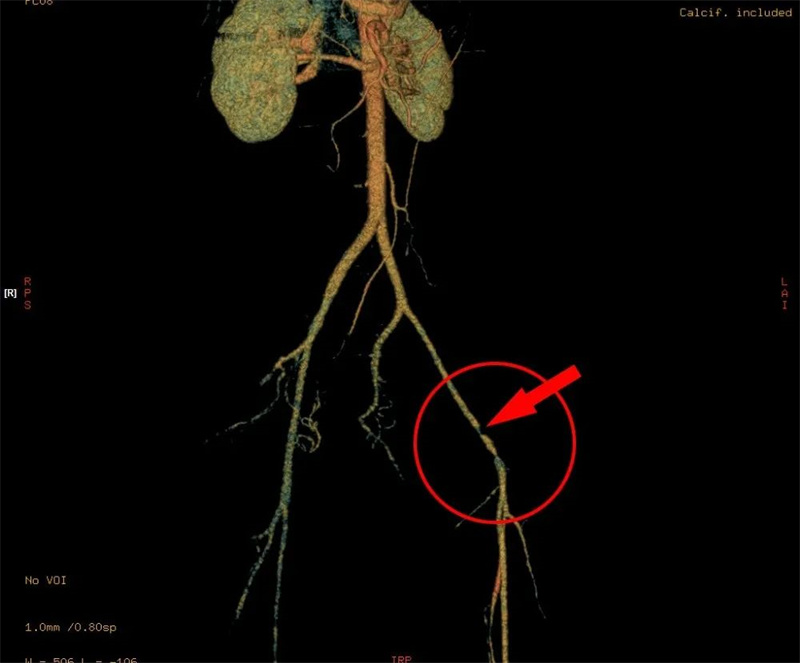

王女士精神好转、面色红润,血压109/72mmHg趋于稳定,但其双下肢麻木无力,肿胀逐渐加重,考虑骨折压迫神经,行床旁超声及动脉CTA检查进一步明确患者左侧髂外静脉断裂、髂外动脉狭窄,如髂外动脉完全闭塞,下肢缺血将面临截肢风险,救治危机尚未解除。

▲CTA显示左侧髂外动脉严重狭窄

“患者骨盆骨折双侧骶髂关节脱位,前环后环均不稳定,伴随右侧腰骶干神经损伤,髂外动静脉血管损伤,手术的难度高,极具挑战性。”荆门市人民医院创伤骨科主任施能兵介绍,科室立即实施加速康复外科(ERAS)临床路径管理,并利用3D打印技术还原骨折模型,制定个性化手术方案。

3天后,施能兵带领的创伤救治团队为王女士成功实施了“左侧骶髂关节脱位切开复位内固定术+左侧髂外动静脉控查修复术+右侧腰骶干探查松解术+右侧骶骨骨折、骶髂关节脱位复位内固定术+双侧耻骨骨折切开复位内固定术”。

术后,王女士生命体征稳定。骨盆稳定、血管血流再通,受压迫的神经出得到了松解,下肢麻木不适明显减轻,肿胀明显消退,下肢力量逐渐恢复。